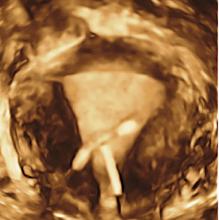

In Part 2 of this 3-part video series on recent advancements in diagnostic radiology, current editorial advisory board member Robert L. Bard, MD, PC, DABR, FASLMS, talks with ITN on the advantages of using power Doppler Sonography as a non-invasive way to screen for prostate tumors with abnormal blood vessels.

Dr. Bard is internationally known and recognized as a leader in his field. He specializes in advanced 3-D Doppler imaging to detect cancers in numerous organs, including the breast, prostate, and other areas. His images are used to accurately guide biopsies, target therapy and provide focused follow-up after treatment. He is committed to improving non-invasive cancer testing and developing minimally invasive image guided technologies to prevent cancer spread.

Imaging advancements, including 3D Doppler imaging to detect cancers in numerous organs, are used to accurately guide biopsies, target therapy and provide focused follow-up after treatment. ITN spoke with current editorial advisory board member Robert L. Bard, MD, PC, DABR, FASLMS, to find out more about recent advancements in diagnostic radiology. This video is Part 1 of a 3-part video series.